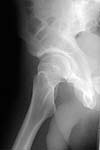

i'd like to see post reduction x-rays to assess congruency of the reduction including AP & both Judet views. If the fragment is truly small, and extra-articular and the joint is stable, probably nothing needs to be done with the fragment, but i'd like more views! thanks

Here are the missing postreduction views.